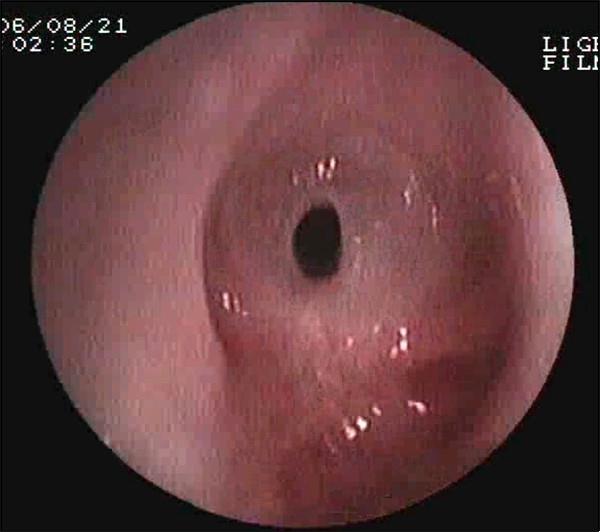

常見(jiàn)的鏡下改變:

聲門(mén)下狹窄

氣道狹窄